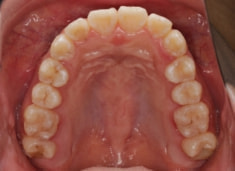

治療前

治療後(1年12ヶ月後)